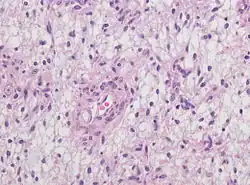

Neuropathology

Neuropathology is a specialty within the study of pathology focused on the disease of the brain, spinal cord, and neural tissue.[32] This includes the central nervous system and the peripheral nervous system. Tissue analysis comes from either surgical biopsies or post mortem autopsies. Common tissue samples include muscle fibers and nervous tissue.[33] Common applications of neuropathology include studying samples of tissue in patients who have Parkinson's disease, Alzheimer's disease, dementia, Huntington's disease, amyotrophic lateral sclerosis, mitochondria disease, and any disorder that has neural deterioration in the brain or spinal cord.[34][35]

While pathology has been studied for millennia only within the last few hundred years has medicine focused on a tissue- and organ-based approach to tissue disease. In 1810, Thomas Hodgkin started to look at the damaged tissue for the cause. This was conjoined with the emergence of microscopy and started the current understanding of how the tissue of the human body is studied.[36]